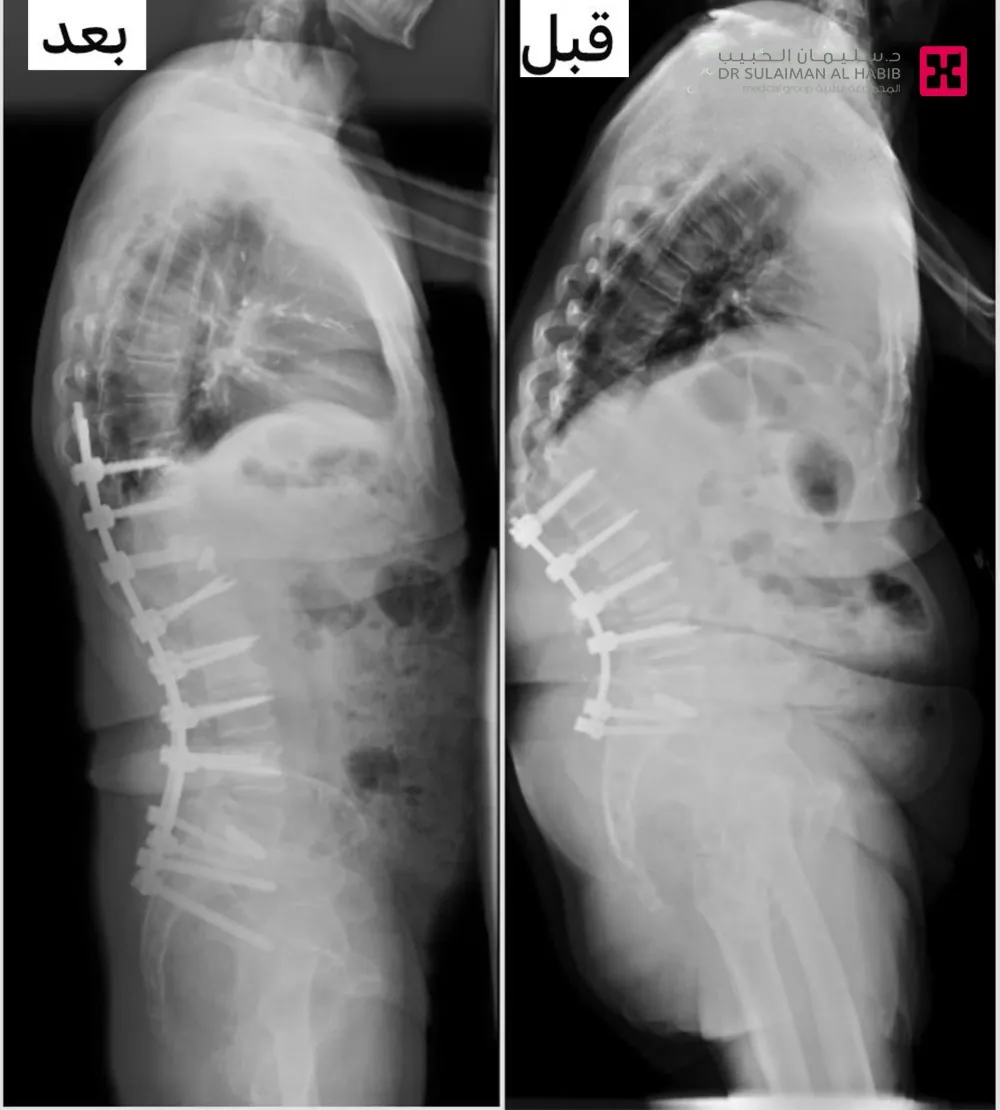

الذي قال أن المراجع زار المستشفى وهو يشتكي من انحناء مفرط للأمام في أعلى الظهر وتشوه في المظهر، مع آلام وصعوبة شديد بالوقوف والمشي. فتمت معاينته واخضاعه لعدة فحوصات دقيقة شملت، الأشعة السينية والأشعة المقطعية، إضافة إلى الرنين المغناطيسي، لتبيان ما إذا كان العمود الفقري مصاباً بالكسور، وأجريت له كذلك اختبارات الأعصاب، وقياس كثافة العظام. وقد أظهرت النتائج وجود كسر بالفقرات المتجاورة، بالإضافة إلى تحدب حاد بدرجة “80”.

واستطرد د. السالمي الحاصل على البورد والزمالة الفرنسية، أن الفريق الطبي درس الحالة، وخلص إلى أن هناك حاجة ماسة للتدخل الجراحي، وبالفعل أجريت له عملية دقيقة جرى فيها تثبيت الكسور، وتمديد الثبيت باستخدام المسامير المدعمة بالإسمنت الطبي من خلال التدخل المحدود، وتعديل التحدب واستغرقت العملية “4” ساعات، واستخدمت فيها تقنيات حديثة كالملاحة العصبية وتكللت جهود الفريق الطبي بالنجاح التام، ونقل المراجع إلى جناح التنويم وتحسنت حالته باضطراد مع الرعاية الطبية الحثيثة، والعلاج التأهيلي، إضافة أنه تخلص من الآلام واستعاد مظهره ومشيه الطبيعي، وعاد لممارسة حياته بصورة طبيعية.